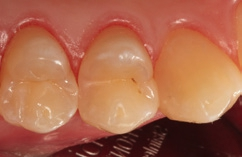

Fall 5 Minimalinvasive Slot-Versorgung an Zähnen 13 und 14

Die Zähne 13 und 14 des 19-jährigen Patienten zeigten aktive Primärläsionen, die Anzeichen der hohen Kariesaktivität des jungen Patienten waren (Abb. 20). Beide Kavitäten wurden mit dem Komet Mikropräparationsinstrument 8830M.314012 präpariert und die approximalen Flanken mithilfe eines diamantierten, wabenförmigen Feinkornfinierstreifens WS 25F (Komet Dental) geglättet. Die Abbildung 21 zeigt die beiden präparierten Kavitäten mit bereits angelegten Palodent V3-Spannringen und Teilmatrizenfolien. Der distal gelegene Spannring wurde von seinem Ringdurchmesser nach distal orientiert, um eine bessere Zugänglichkeit zu den beiden Kavitäten zu gewährleisten. Gerade im Prämolarenbereich ist dieses Vorgehen oftmals sehr hilfreich. Die Abbildung 22 zeigt die fertige Versorgung mit SDR flow+ in der Farbe A2 nach adhäsiver Vorbehandlung mit Prime&Bond active nach Schmelzkonditionierung mit Phosphorsäuregel. Generell ist bei den Universaladhäsiven der selbstkonditionierenden Vorbehandlung des Dentins der Vorzug zu geben. Eine selektive Schmelzätzung bei so schmalen und kleinen Kavitäten ist aber nicht so einfach umzusetzen. Ein Pluspunkt bei allen Universaladhäsiven ist deren Toleranz auf eine vorangegangene Ätzung des Dentins mit Phosphorsäuregel: Diese „Etch&Rinse“-Anwendung hat keinen negativen Einfluss auf die Randintegration und die Haftung. Eine Metaanalyse zu Universaladhäsiven attestiert den milden Universaladhäsiven sehr gute Haftwerte auf Dentin im selbstkonditionierenden Modus [48]. Eine zusätzliche Phosphorsäurekonditionierung ergibt hier keine Vorteile, da die Dentin-Haftwerte sich im selbstkonditionierenden und „Etch&Rinse“- Modus nicht unterscheiden [10,56], aber auch keine Nachteile. Auch dieses Beispiel zeigt die gute Farbadaptation und Randintegration des Bulk-Flow-Komposits.